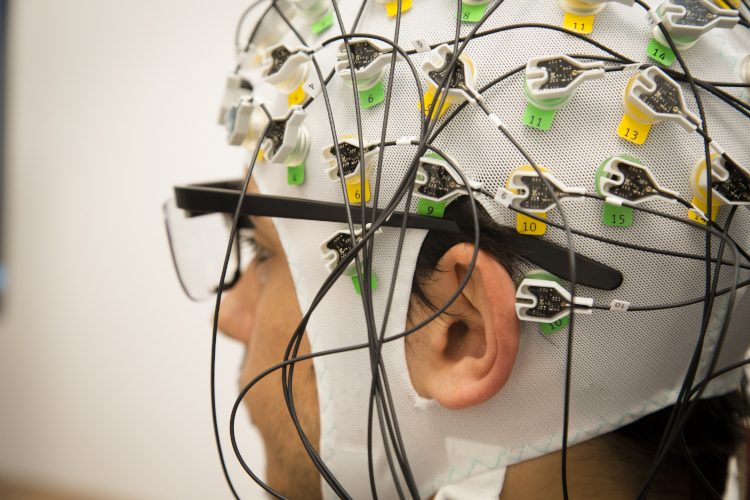

Center for Advanced Biomaterials for Health Care

Interdisciplinary Research Centre on Biomaterials (CRIB), Naples

The Center for Advanced Biomaterials for Health Care (CABHC) develops materials and technologies to engineer bio-logically inspired platforms and systems for applications in the biomedical sector.